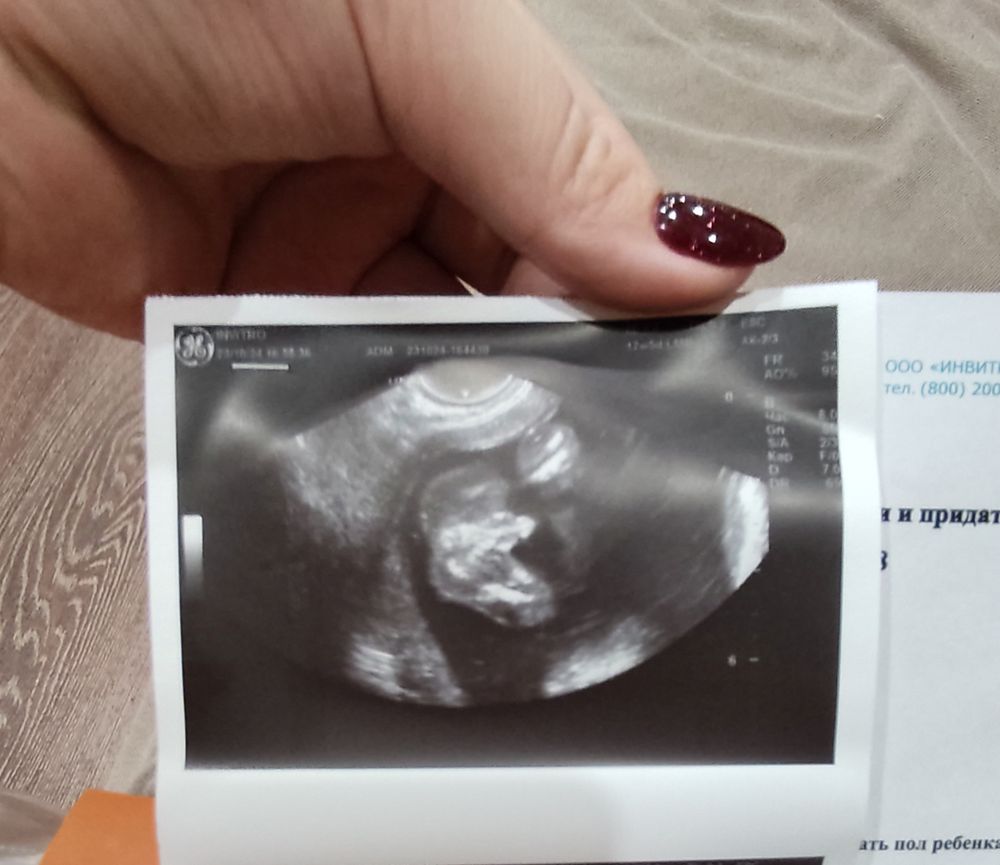

Алёна Абрамова в Благополучная беременность год Пол ребенка на 17 неделе Пол малыша Как думаете какой пол Посмотрите еще 20 записей на эту тему Лучший ответ Татьяна Если на снимке то, о чем я думаю, то мальчик) 23.10.2024 Ответить Отменить Ответить Сашуля Мужской пол 23.10.2024 Ответить Весна Мальчик 100% 23.10.2024 Ответить Ирина Понарошку Я конечно не узист,но вижу мальчика 23.10.2024 Ответить Святая инквизиция Мальчик 23.10.2024 Ответить Катя Мальчик конечно) 23.10.2024 Ответить Пол в 12 недель Когда увидели пол на узи Чаты Беременных Выберите чат: Январята-2026 Февралята-2026 Мартята-2026 Апрелята-2026 Майчата-2026 Июнята-2026 Июлята-2026 Августята-2026